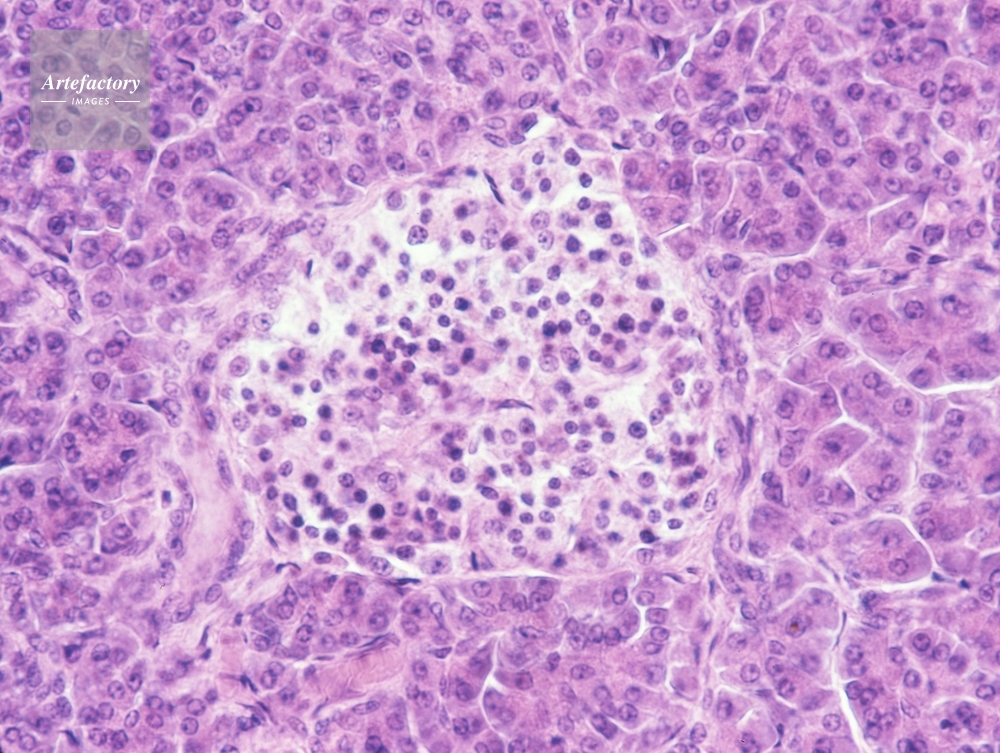

| 作品タイトル | ランゲルハンス氏島・人のすい臓 | モデルリリース | なし | |

| キャプション | 顕微鏡倍率×200 ヘマトキシリン・エオシン染色 | 制限事項 | ||